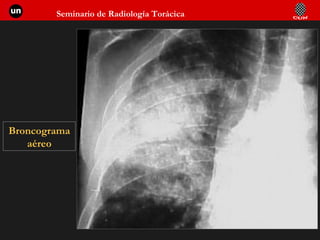

AFECTACION ALVEOLAR  SIGNOS  CLASICOS Broncograma / alveolograma aéreo  Nódulos acinares  Bordes mal definidos  Tendencia a la confluencia  Distribución lobar o segmentaria Alas de mariposa  Aparición precoz tras síntomas

Broncograma aéreo